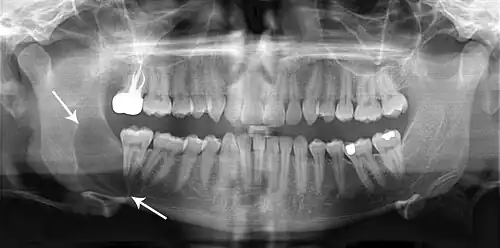

Radiograficamente, o QO se caracteriza como uma lesão radiolúcida uni ou multilocular, de bordas bem delimitadas e halo esclerótico, podendo ou não estar associada a um dente incluso.[4] Lesões maiores tendem a ter um aspecto multicístico festonado (aspecto de "bolha de sabão" ou de "favo de mel"), enquanto lesões menores tendem a ser unicísticas.[4] As lesões podem apresentar comportamento agressivo, com reabsorção óssea e dos dentes, deslocamento dos dentes e expansões ósseas.[5] Cerca de 25 a 40% dos queratocistos são associados a dentes inclusos.[4] Queratocistos menores podem ser confundidos com cisto dentígero, cisto radicular ou cisto periodontal lateral.[6]

O diagnóstico do QO se dá pelo exame de imagem e exame anatomopatológico.[8] Além da radiografia panorâmica, a TCFC é utilizada para o planejamento cirúrgico da lesão, especialmente para lesões extensas.[8]